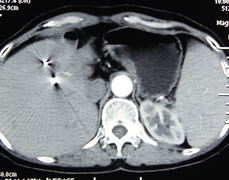

2021年8月20日,吃过晚饭的卢奶奶正和往时一样,和家人高兴的观看电视,但突如其来的腹痛打破了这个温馨的气氛。卢奶奶突然感觉到上腹部剧烈...